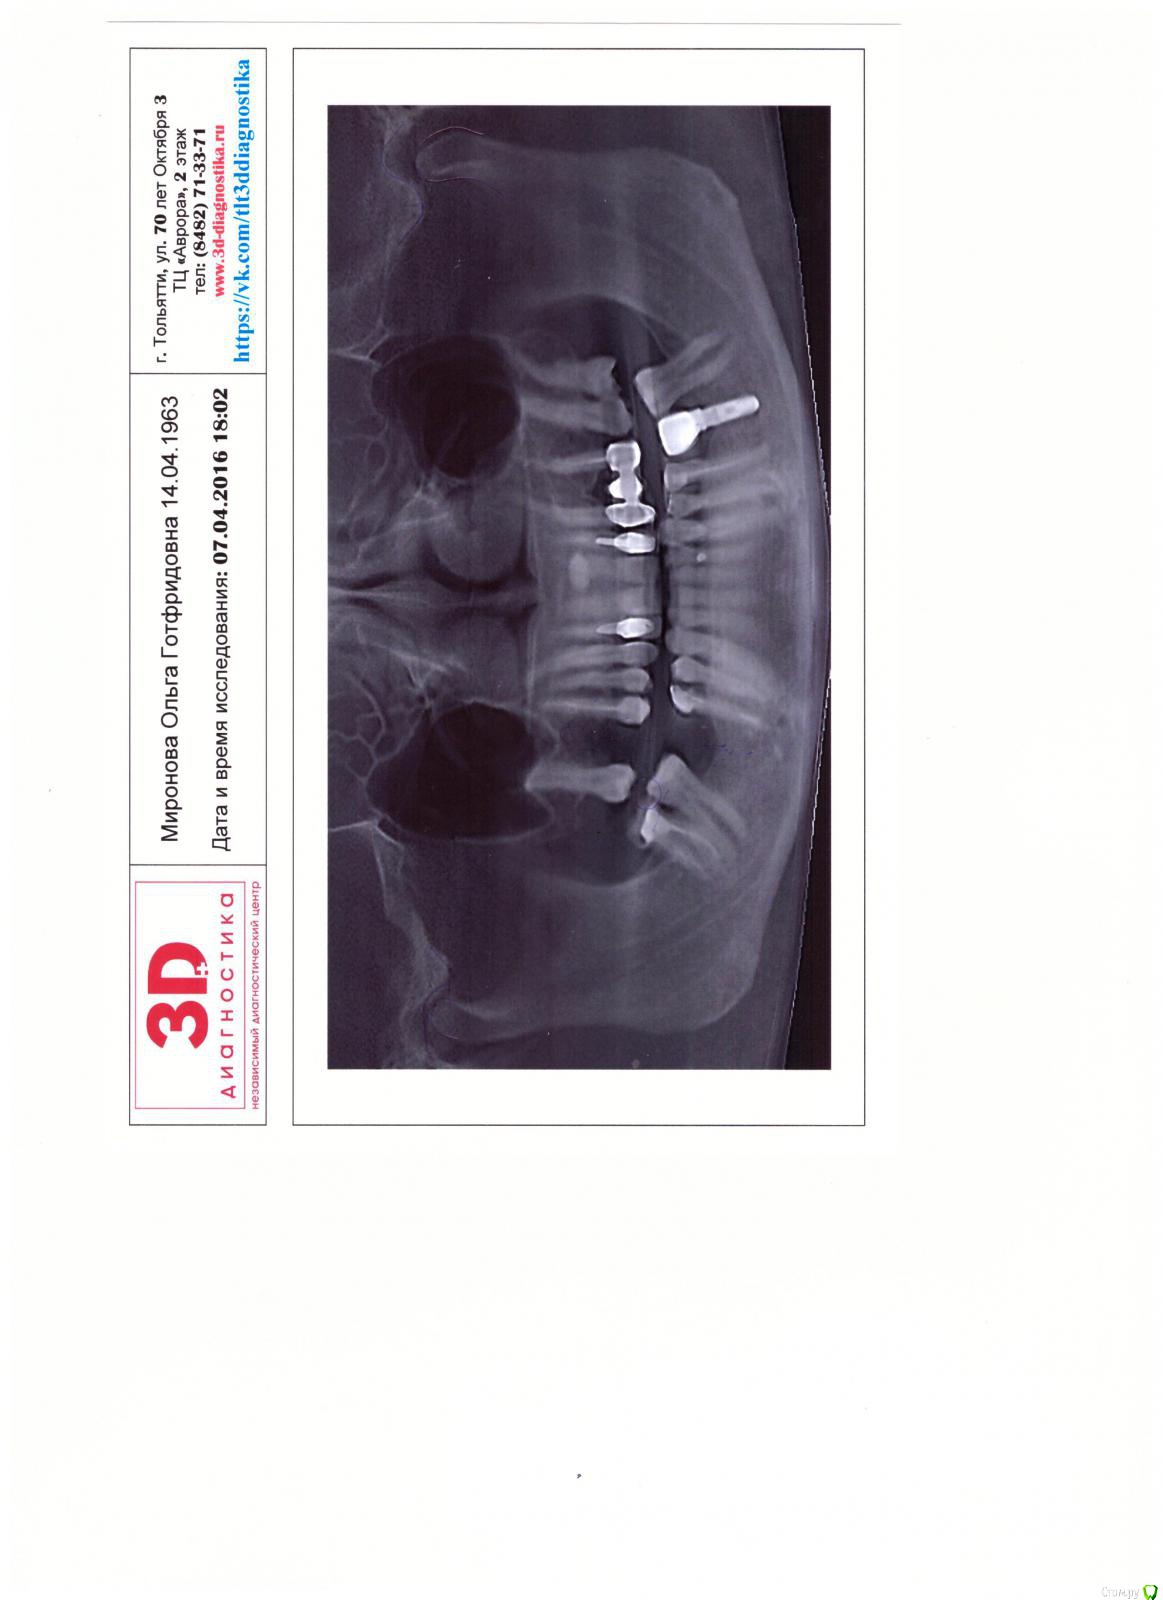

OLG Опубликовано 30 августа, 2016 Поделиться Опубликовано 30 августа, 2016 Здравствуйте,коллеги.Пациент из Америки ставил имплантаты давно. Может кто-то узнает, что за фирма? Ссылка на комментарий

OLG Опубликовано 30 августа, 2016 Автор Поделиться Опубликовано 30 августа, 2016 Извините, что кверх ногами. не знаю как перевернуть. Ссылка на комментарий

pit Опубликовано 30 августа, 2016 Поделиться Опубликовано 30 августа, 2016 Здравствуйте,коллеги.Пациент из Америки ставил имплантаты давно. Может кто-то узнает, что за фирма?Анкилос 4 Ссылка на комментарий

IvanK Опубликовано 31 августа, 2016 Поделиться Опубликовано 31 августа, 2016 Анкилос+1 1 Ссылка на комментарий

Чертков Александр Опубликовано 31 августа, 2016 Поделиться Опубликовано 31 августа, 2016 Анкилос+1 Ссылка на комментарий

faity Опубликовано 31 августа, 2016 Поделиться Опубликовано 31 августа, 2016 +1 Ankylos Ссылка на комментарий